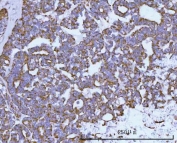

IHC staining of FFPE human lung adenocarcinoma tissue with HRPAP20 antibody. HIER: boil tissue sections in pH8 EDTA for 20 min and allow to cool before testing.